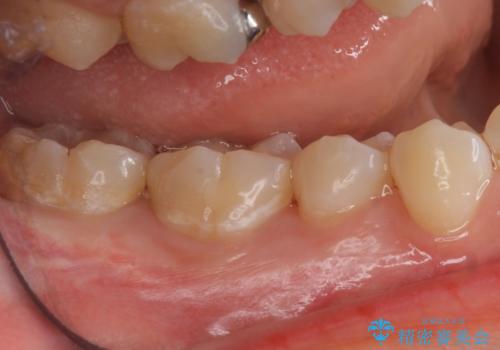

メンテナンスで虫歯を発見することができたため、症状が出る前に治療を終えることができました。下の奥歯は笑った時に外からよく見える部分なので白く目立たない詰め物を入れることができて大変喜んでいただけました。

放置していくとインレーでの修復が難しくなってしまうため、定期的なメンテナンスが大事になってきます。